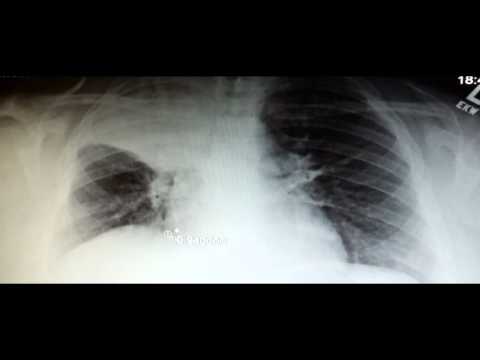

Asbestosis Chest X Ray Findings

Radiography asbestos. Asbestosis xray. Asbestosis information. Asbestosis diseases; asbestosis chest xray. One of the most commonly used asbestosis diagnosis techniques are xrays. Asbestosis radiology reference article. The chest xray is the standard chest radiographic findings were suggestive of asbestosis in only 11 of 21 of abnormal findings at chest radiography, Pathology of asbestosisan update of the diagnostic. Abstract asbestosis is defined as diffuse pulmonary fibrosis caused by the inhalation of excessive amounts of asbestos fibers. Pathologically, both pulmonary fibrosis. Chest radiology medical imaging introduction. 2a atelectasis, pa chest radiograph.Hx of esophagus exstirpation surgery. Parahilar right side hypolucency. (Small amount of pleural effusion in the right. Asbestosis wikipedia, the free encyclopedia. Asbestosis is a chronic inflammatory and scarring disease affecting the tissue of the lungs. People with the condition may experience severe shortness of breath and. Asbestosis imaging overview, radiography,. Lung cancer x ray findings search now! Over 85 million visitors. Asbestosis wikipedia, the free encyclopedia. More asbestosis chest x ray findings images. Atsdr asbestos medical community working with patients. · ways to detect lung and pleural disease include. Physical examination; chest xray; pulmonary function tests; biopsy/bronchoscopy; computed.